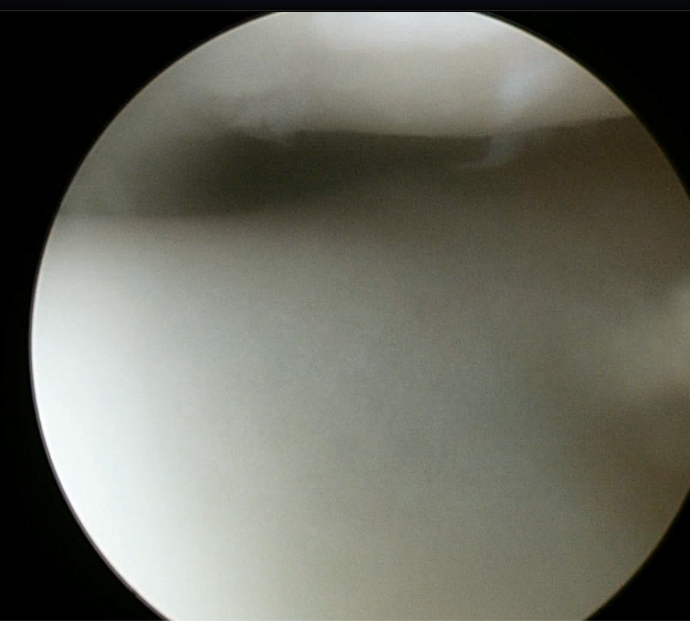

正常的关节软骨表面平整、光滑。

髌股关节失稳进行性发展后,关节镜下见髌骨软骨剥脱、软骨下骨硬化,骨关节炎形成。